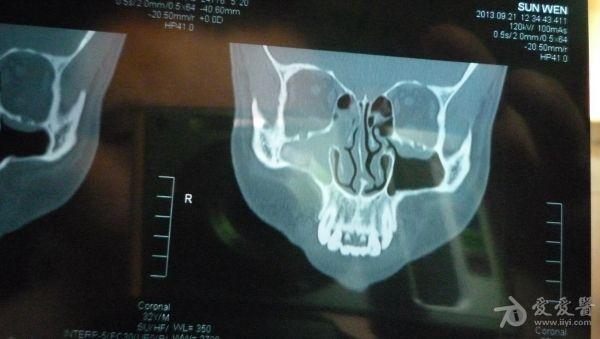

CT结果是右侧上颌窦及部分筛窦窦腔内见稍高密度影填充,CT值约21U,窦壁骨质未见破坏征象;鼻腔后部亦见少量稍高密度影填充;左侧上颌窦、筛窦及蝶窦、额窦未见明显异常。CT图片见附件。医生说我的右边鼻窦都被软组织堵死了,必须要做手术清楚后再做病理分析看是良性还是恶性。

想请问下医生:CT图片上右边的上颌窦内的稍高密度影,是软组织还是液体的几率大些呢